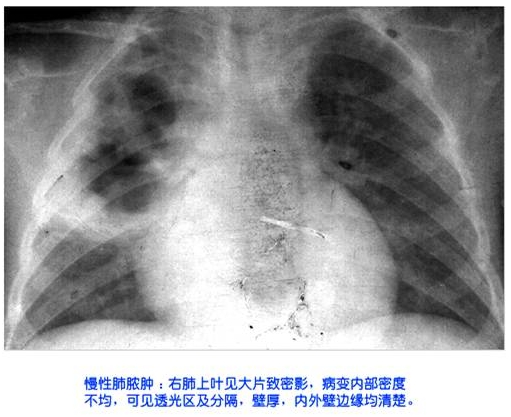

照片名称:慢性肺脓肿